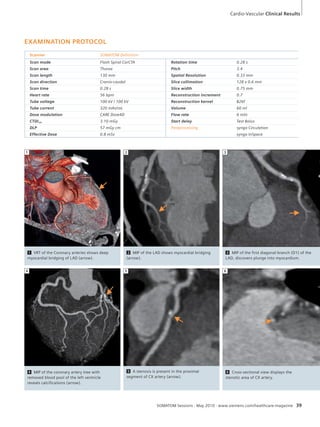

In this case, the setting with 96 mm of

z-direction coverage (and 1.5 seconds

temporal resolution) covered nearly the

entire supratentorial brain. syngo VPCT

Neuro extracts first-pass data from the

45 seconds dynamic acquisition en-abling

a rapid exam. The extents of both

the salvageable ischemic penumbra and

the irreversible infarct core were fully

depicted. Rescue of ischemic penumbra

is the main rationale for aggressive

stroke intervention, and its identification

through perfusion imaging may form the

basis of patient selection for therapy in

the near future.

SOMATOM Sessions · May 2010 · www.siemens.com/healthcare-magazine 51

DIAGNOSIS

While NCCT showed only subtle blurring

of the normal gray/white matter inter-face

at the left frontal operculum, CTP

with extended coverage revealed the full

extent of the acute ischemia in the ante-rior

left middle cerebral artery (MCA)

territory. There was severe compromise

of cerebral blood flow (CBF) to the mid

and inferior left frontal lobe. At the level

of the operculum (Broca’s area), there

was a matched defect in low CBF and

low cerebral blood volume (CBV) indica-tive

of irreversible infarct core (Fig. 1).

However, there was appreciable CBF/CBV